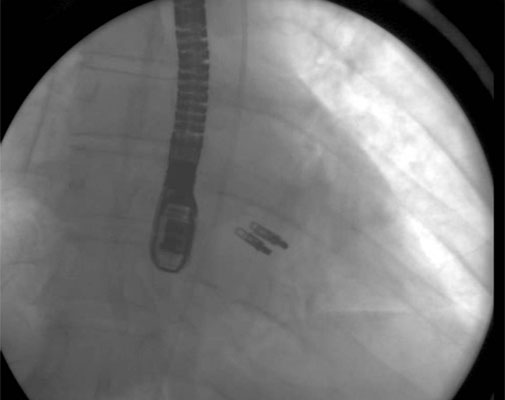

4. From the right femoral venous puncture, a TEE guided trans-septal puncture of the septum is performed using a standard transseptal kit (Figure 7) with the Brockenbrough needle, a dilator and a Mullins sheath. The site of the puncture is decided using a standardized approach which optimizes the maneuverability of the delivery system. The puncture is usually high and posterior in the fossa ovalis. After successful septal puncture, the Mullins sheath is parked in the left atrium and the patient is heparinized to achieve an ACT of at least 250 seconds.